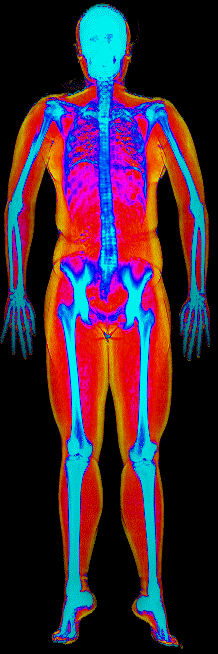

This page features real, anonymized DEXA scan images from BodyStats clients, organized by gender and body fat percentage in 5% increments. DEXA (Dual-Energy X-ray Absorptiometry) is the clinical gold standard for measuring body composition — far more accurate than scales, calipers, or visual estimates.

Each colorized scan shows the distribution of fat tissue (shown in warmer colors) and lean tissue (cooler colors) throughout the body. Compare your own DEXA scan to others in your range, or see what different body fat levels actually look like on a scan.

Male DEXA Scans by Body Fat %

15 to 20% body fat